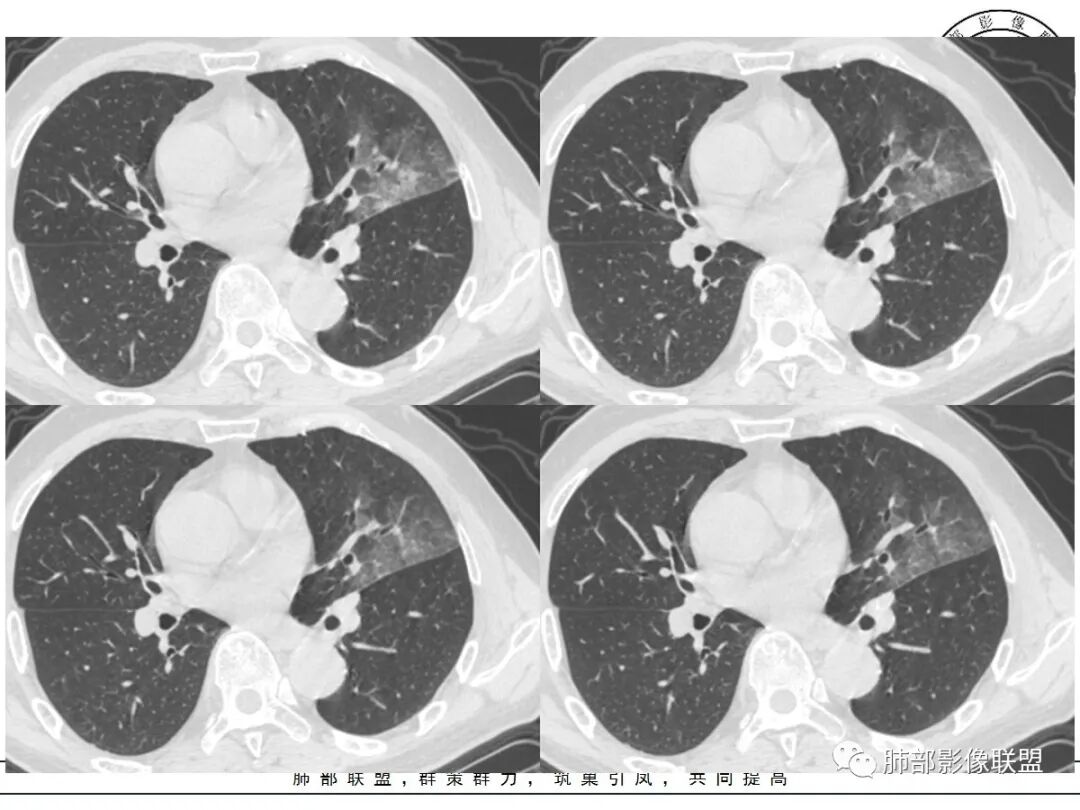

左肺上叶类圆形软组织影,边界较清楚,其内密度均匀,外侧缘可见空气新月征,并可见点状钙化,增强扫描可见均匀强化,病灶周围可见磨玻璃渗出性密度影,斜裂侧光滑平整。考虑炎性病灶,以肉芽肿性炎症为主(如真菌性肉芽肿),鉴别结核(无卫星灶,无多态性),肺癌(无毛刺,分叶等恶性征象,)细菌性炎症(密度一般不这么致密,很少钙化及空气新月征)。

左肺上叶类圆形软组织影,界清,内见空洞影,病灶周围斑片影,可见空气支气管征,未垮叶。考虑炎性病变,糖尿病四大金刚,肺克?毛霉?

老年男性,血糖升高六年,反复咳痰咳嗽3周,左肺上叶近斜裂类圆形肿块影,边缘伴磨玻璃影,边界不清。内部可见支气管走行、钙化、小空洞,叶间裂局部膨隆,增强扫描轻度强化,内部可见小的低密度区,边界尚清。考虑为炎性病变可能性大。

左肺叶裂旁实变影,宽基底与叶裂胸膜相连,边缘平直,部分略膨隆,病灶近段及上段支气管深入病灶内,部分壁略增厚,远端支气管截断,似有小空泡,壁规则,内部可见高密度钙化,周围可见模糊的GGO,血象正常,考虑结核(NTM),鉴别隐球菌,奴卡,放线菌。

老年男性,66,反复咳嗽、咳痰3月。糖尿病,血象不高。

胸部CT:左肺上叶类圆形肿块影,边界较清楚,密度较均匀,内可见小片坏死、偏心空洞、空气新月征、点状钙化,周围晕、絮状渗出、边缘模糊,支气管扩张、充气征、支气管进入病灶堵塞,叶裂牵拉明显,增强扫描中度均匀强化,纵隔可见淋巴结。考虑:炎性病灶,肉芽肿性炎症,曲霉?毛霉?鉴别:TB,淋巴瘤。

左上肺类圆形肿块影,边界较清楚,支气管通畅略扩张,周围磨玻璃影,其内密度均匀,外侧见空气新月征,且见点状钙化。叶间裂光滑稍膨隆。老年男性,糖尿病,高血压,痰培养克雷伯菌。综合考虑炎性病灶,克雷伯合并真菌感染,曲霉。结核合并真菌。鉴别肺癌合并感染。

左肺上叶类圆形软组织影,边界稍模糊,其内密度均匀,外侧缘可见空气新月征,并可见点状钙化,增强扫描渐进性强化,病灶周围可见磨玻璃影,斜裂侧光滑平整,气管未见明显闭塞,淋巴结未见肿大,糖尿病患者,首先考虑感染性变,结核并曲霉?